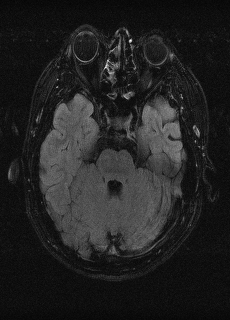

As we observe from the right image in Fig. 2, our BRM, both from MIMO and SISO settings, predicts the performance of dedicated models with a high correlation. We further choose the best three , and perform the last stage of fine-tuning accordingly to (6). A visual evaluation on real data is shown in Fig. 3. For simulated data, please refer to the Supplemental Material section.

Base on the best performing , we perceive that among , , and FLAIR, the results are best when is sampled the most. We suggest that this makes intuitive sense as images provide the best contrast out of the three sequences, which can compensate for the details lost in other images. The same observation can be made on the simulated data, where both and FLAIR show good contrast. When the time setting is changed to non-uniformity, we can see that our search for the best sampling strategy reflects the change. is sampled more as a result of faster acquisition time, while is still sufficiently sampled.

(a) 34.38/0.9371

(a) 34.38/0.9371

|

(b) 42.42/0.9883

(b) 42.42/0.9883

|

(c) 44.60/0.9920

(c) 44.60/0.9920

|

(d) 45.50/0.9940

(d) 45.50/0.9940

|

(e) PSNR/SSIM

(e) PSNR/SSIM

|

|

(f) 29.74/0.8903

(f) 29.74/0.8903

|

(g) 36.25/0.9734

(g) 36.25/0.9734

|

(h) 36.42/0.9752

(h) 36.42/0.9752

|

(i) 37.70/0.9832

(i) 37.70/0.9832

|

(j) PSNR/SSIM

(j) PSNR/SSIM

|

|

(k) 39.89/0.9311

(k) 39.89/0.9311

|

(l) 43.94/0.9864

(l) 43.94/0.9864

|

(m) 44.74/0.9883

(m) 44.74/0.9883

|

(n) 45.49/0.9894

(n) 45.49/0.9894

|

(o) PSNR/SSIM

(o) PSNR/SSIM

|